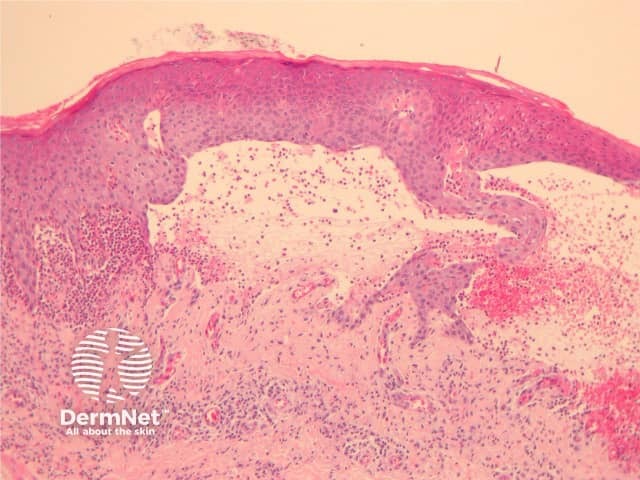

Early lesions during the urticarial phase may be non-specific and show mild upper dermal oedema with perivascular infiltrate (figure 1). There are often conspicuous eosinophils. Immunofluorescence is very helpful in this early phase.

Figure 1

Established blister: The blister is subepidermal and contains fibrin and large numbers of inflammatory cells including eosinophils (figures 2, 3). The eosinophils may be very dense in areas and form small abscesses in the superficial dermis.

Figure 2